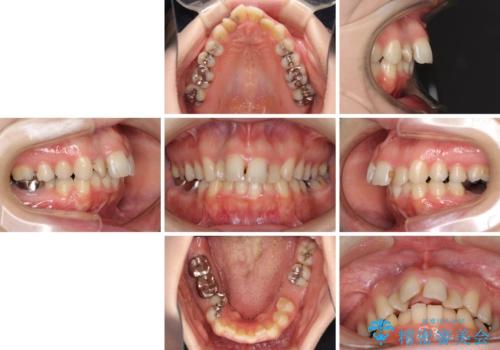

飛び出した上顎前歯とむし歯の多い歯列 目立たないハーフリンガル矯正とむし歯治療

- 上顎前歯が叢生により前方に出ている状態や、全体的なむし歯を気にして来院された患者様です。

全体的にむし歯や欠損が多く、矯正治療とは別に処置が多く必要な口腔内でした。

口元の突出感を改善するために小臼歯4本を抜歯することとしましたが、左下は大臼歯が欠損していたため、そのスペースを活用し、小臼歯を3本抜歯して治療を行うこととしました。

目立たないハーフリンガル矯正を希望され、裏側装置はどうしても清掃性が低下し、むし歯発生のリスクが高まるため、矯正治療前にしっかりとむし歯治療を行い、矯正治療後にセラミックによる補綴治療を行うこととしました。

抜歯したスペースがなかなか閉じず、治療に時間はかかりましたが、術前術後のむし歯治療と合わせて3年10ヶ月で治療を終えることができました。

途中結婚により遠方に引っ越しをされたため、むし歯治療は取り急ぎ目立つところをセラミッククラウンとしましたが、今後落ち着いてきたら他の部分も行っていく予定です。